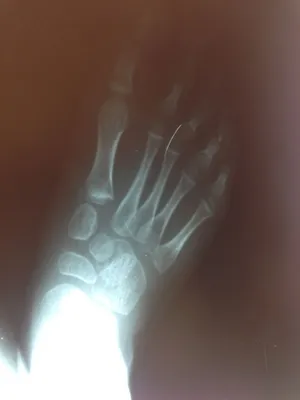

Pre-operative x-rays of the flatfoot with the talus deviated medially due to subluxing off the calcaneus causing the midtarsal joint to sublux laterally and uncovering of the talar head at the talo-navicular joint (left). The talus bone should line up with or be close to paralletl with a line drawn through the 1st metatarsal shaft (right). This is referred to as Meary's angle.

One case see an improvement in Meary's angle after surgical repair of the flatfoot with a subtalar joint implant which blocks the subluxation of the talus off of the calcaneus.